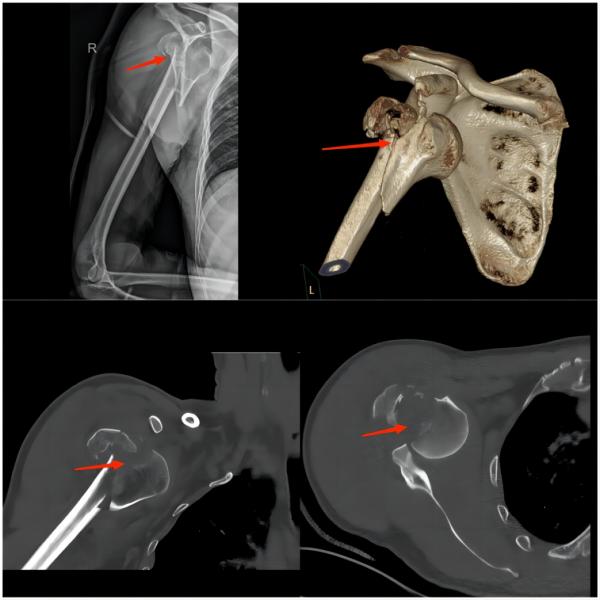

⑤肩部损伤

运动损伤知识科普宣传内容,关于足球运动损伤调查问卷

(上图为右肱骨粉碎性骨折伴肩关节脱位)

常见原因:比赛中球员大力射门,守门员奋力扑救,这种巨大外力易导致守门员肩部损伤,如肩关节脱位及骨折。